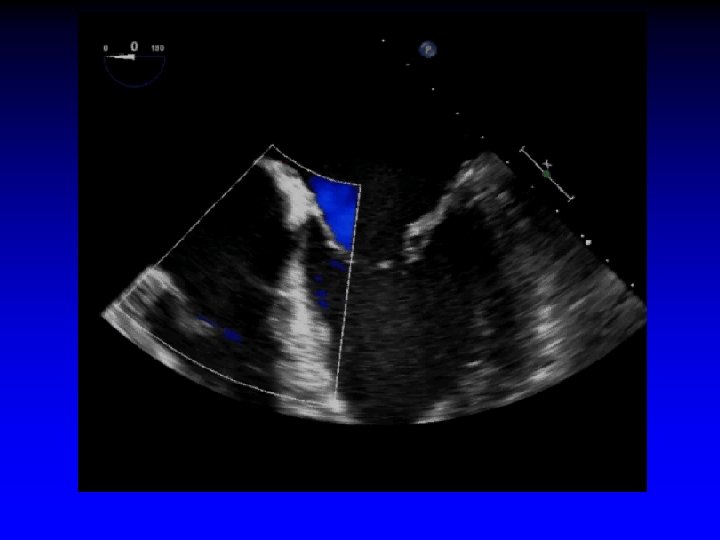

Functional Mitral Regurgitation • Global LV dysfunction • Regional LV dysfunction • Sphericity of LV • Excessive pap muscle displacement • Decreased overlap of leaflets • LA enlargement • Loss of systolic mitral annular contraction • Increased “tenting” area • Delayed activation of P-M pap muscle (dyssynchrony)

Ischemic Mitral Regurgitation C B A D Mitral leaflets are tented apically Mitral annulus is enlarged (A-B = 45 mm) Mitral coaptation depth is increased (C-D = 13 mm)